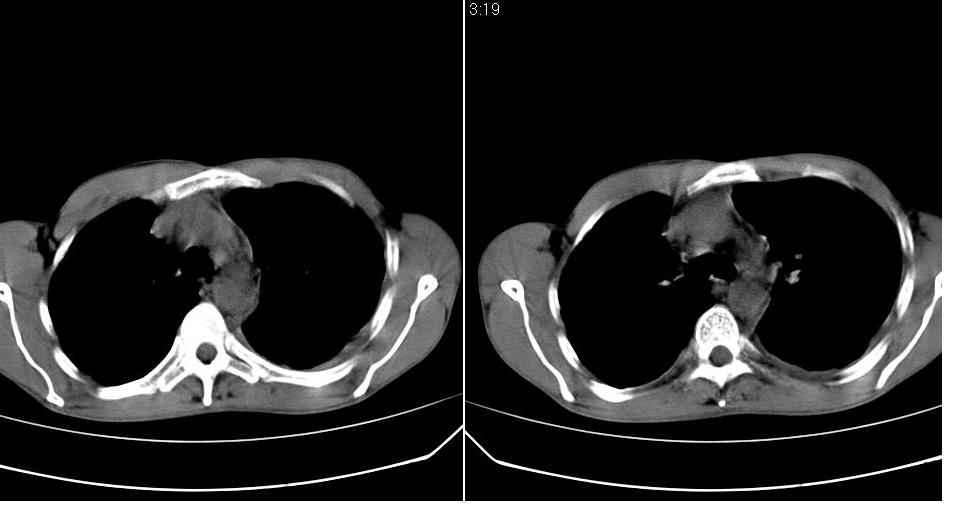

以下是引用苯小孩在2007-6-27 15:09:00的发言:[br]考虑:1、右肺继发性肺结核.2、双侧包裹性积液<胸腔及叶间>3、双侧局部胸膜增厚.[br]建议胸水化验检查.

以下是引用yanghaochen88在2007-6-27 15:08:00的发言:[br]双肺上野散在粟粒状影、包裹性积液、胸膜增厚粘连、叶间积液---tb,至于分型还得结合病史体征细究妥当些。